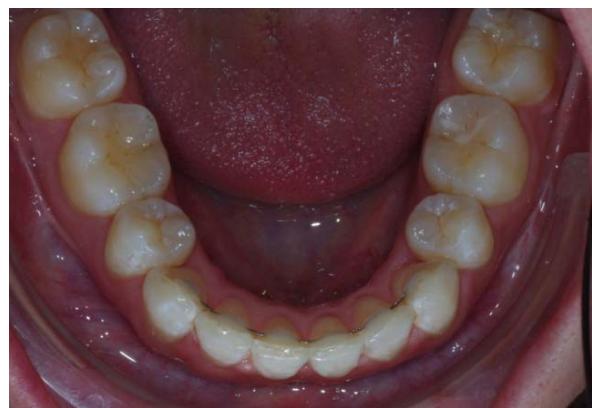

#### Examen endobuccal

L'examen endobuccal montre une supraclusion incisive, une DDM et un sens transversal correct. Dans le sens sagittal, on note une classe Il dentaire.

Examen endobuccal